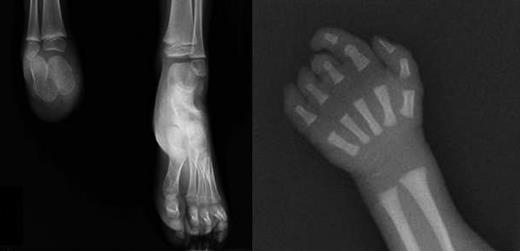

X-rays of limb defects in patients. (Left) Foot x-ray of subject III-1, showing absence of the right foot; the calcaneus and astragalus, that are absent in the father, are present although smaller than the controlateral ones. (Right) X-ray of right hand in subject III-3, showing absence of the last phalange of 2° digit and last 2 phalanges of 3° to 5° digits.

The couple had a second child, a boy with normal platelet count and no limb defects (III-2). During the third pregnancy, chorionic villus sampling was performed at 12 weeks of gestation for advanced maternal age and a unilateral foot defect was detected by ultrasound scan at the time. Cytogenetic analysis showed a normal male karyotype. After delivery, a unilateral digital defect was noted (Figure 2B) and the left foot defect was confirmed (III-3). The platelet count was normal at birth, but increased to more than 700 × 109/L 2 months after delivery.